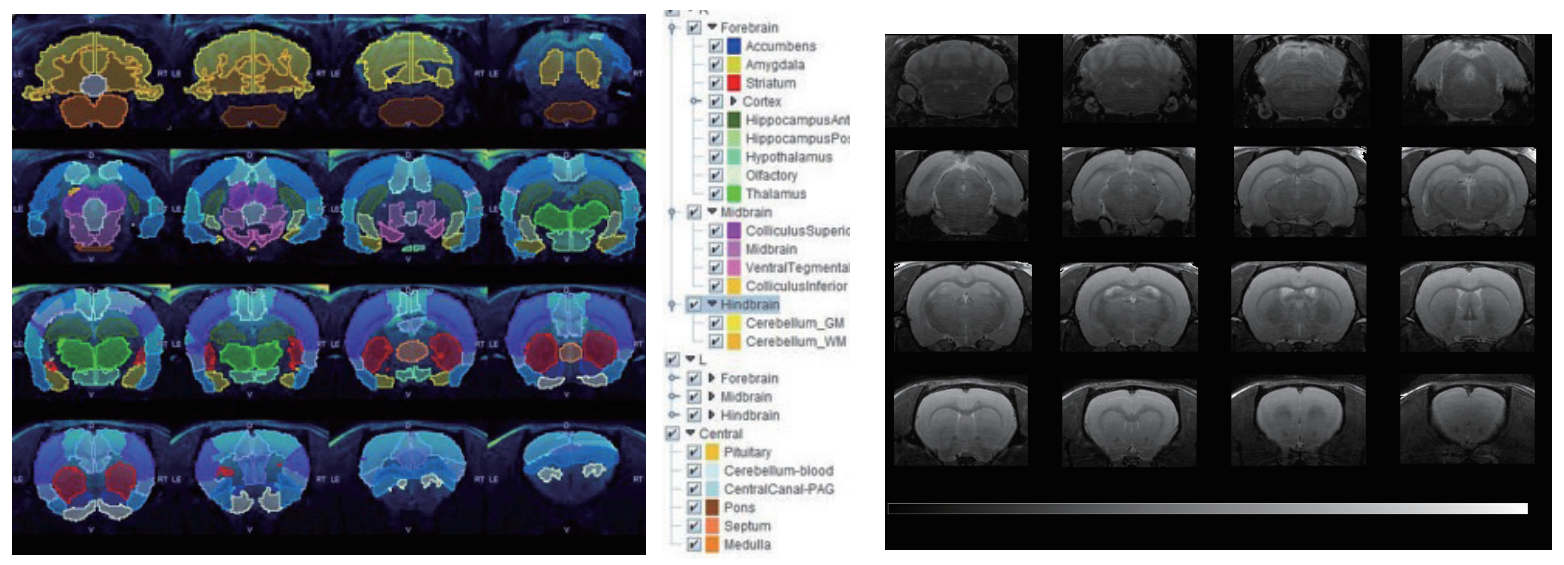

9.4T磁共振的小鼠神經(jīng)成像:A+B)T2加權(quán)RARE影像;C)飛行時(shí)間(TOF)磁共振血管造影和D)ADC圖。結(jié)合高分辨率解剖結(jié)構(gòu)、灌注細(xì)節(jié)和定量擴(kuò)散,這有助于在神經(jīng)系統(tǒng)疾病表征時(shí)提供更全面的信息。

7T磁共振下大鼠腦部RARE影像,使用PMOD軟件分割。